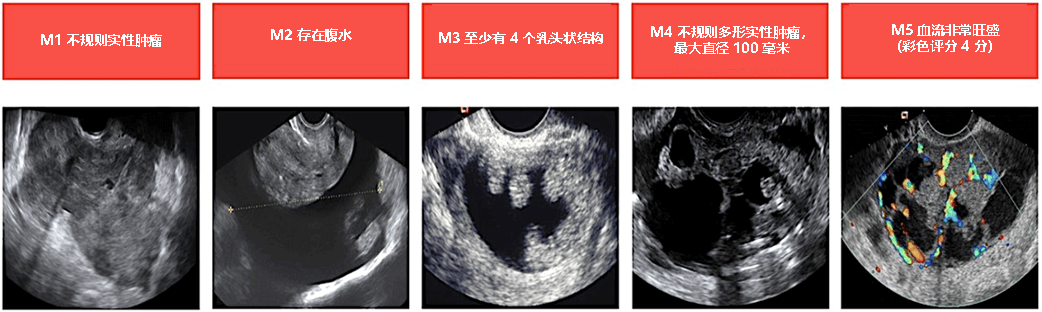

卵巢癌的超声波特征

国际卵巢肿瘤分析(IOTA)小组制定了提示卵巢癌的超声波特征。根据这些超声特征,检测卵巢癌的敏感性可达 95%,特异性可达 91%。(蒂默曼,2010 年)

恶性肿瘤卵巢囊肿的特征: